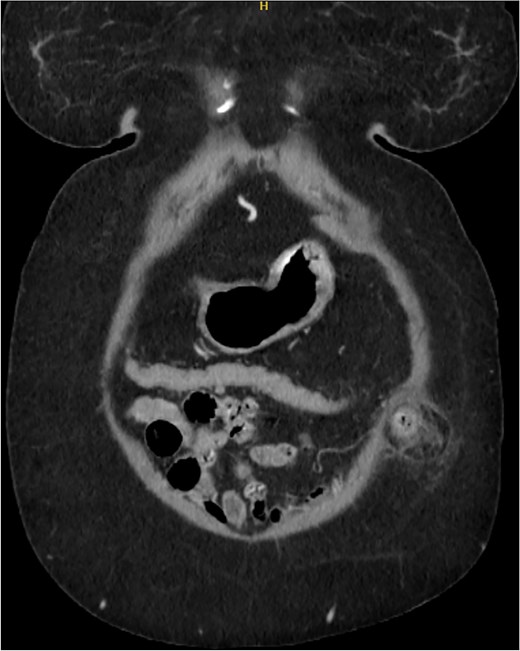

A 76-year-old female with a medical history of type 2 diabetes mellitus (controlled with oral medications), hypertension (on two medications), hyperlipidemia (on atorvastatin), and recently diagnosed Alzheimer’s disease (started on memantine) presented to the emergency department with severe left-sided abdominal pain of 2 days’ duration. The pain began gradually but worsened significantly in the last few hours. It was associated with a bulging mass in the abdomen that was tender and painful to touch. The patient reported that the swelling had been present for 2 years, intermittently reducible with minimal exertion. However, since the previous day, it had become irreducible and increasingly painful, particularly after a failed attempt to reduce it manually at home. She also admitted to chronic constipation for years, usually treated with oral laxatives, though she had not been compliant with them recently. Her surgical history included a laparoscopic cholecystectomy combined with paraumbilical hernia repair using mesh 3 years ago. Upon examination by the on-call surgical team, the patient was afebrile with stable vital signs. Her abdomen was distended, and a 7 × 7 cm irreducible, tender mass was noted over the left side. An urgent computed tomography (CT) scan of the abdomen and pelvis with intravenous and oral contrast revealed a left lateral ventral abdominal hernia traversing the left lateral oblique muscles. The hernia sac contained omental fat and an inflamed diverticulum of the transverse colon, with surrounding inflammatory changes. The defect measured 1.4 × 1 cm, and the hernia sac measured 6.7 × 4.2 × 4 cm. No free fluid, fluid collections, or pneumoperitoneum were identified (Figs 1–3).